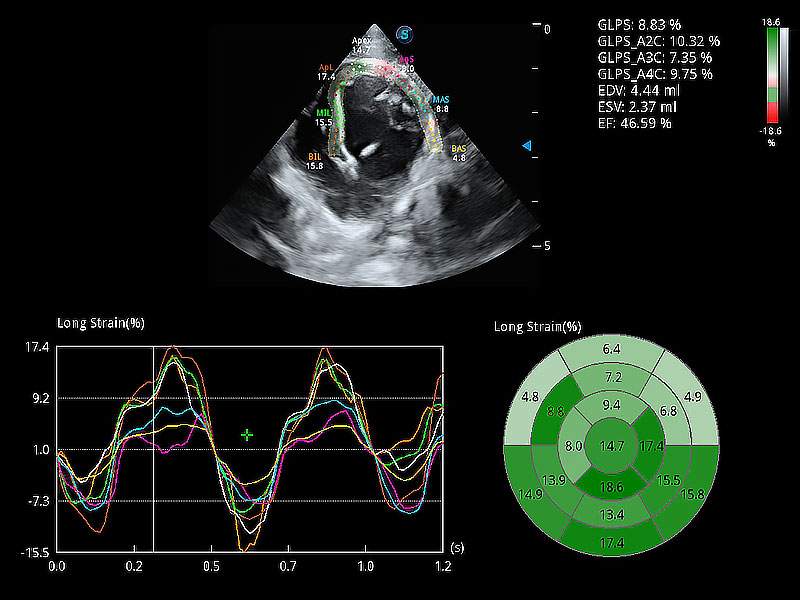

ProPet 80 配備了豐富的心臟探頭群、先進(jìn)的成像技術(shù)和專業(yè)的心臟測(cè)量工具,可幫助動(dòng)物醫(yī)生為不同體型和生理結(jié)構(gòu)的動(dòng)物提供心臟和心肌功能的全面評(píng)估。

通過心肌識(shí)別技術(shù)與二維斑點(diǎn)追蹤技術(shù)相結(jié)合,對(duì)心臟的超聲圖像進(jìn)行量化分析。計(jì)算心肌17個(gè)節(jié)段的應(yīng)變、應(yīng)變率、速度、位移等,并通過牛眼圖的形式進(jìn)行呈現(xiàn)。